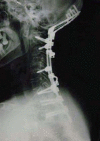

Full-scale three-dimensional (3D) models offer a useful tool in preoperative planning, allowing full-scale stereoscopic recognition from any direction and distance with tactile feedback. Although skills and implants have progressed with various innovations, rheumatoid cervical spine surgery remains challenging. No previous studies have documented the usefulness of full-scale 3D models in this complicated situation. The present study assessed the utility of full-scale 3D models in rheumatoid cervical spine surgery. Polyurethane or plaster 3D models of 15 full-sized occipitocervical or upper cervical spines were fabricated using rapid prototyping (stereolithography) techniques from 1-mm slices of individual CT data. A comfortable alignment for patients was reproduced from CT data obtained with the patient in a comfortable occipitocervical position. Usefulness of these models was analyzed. Using models as a template, appropriate shape of the plate-rod construct could be created in advance. No troublesome Halo-vests were needed for preoperative adjustment of occipitocervical angle. No patients complained of dysphasia following surgery. Screw entry points and trajectories were simultaneously determined with full-scale dimensions and perspective, proving particularly valuable in cases involving high-riding vertebral artery. Full-scale stereoscopic recognition has never been achieved with any existing imaging modalities. Full-scale 3D models thus appear useful and applicable to all complicated spinal surgeries. The combination of computer-assisted navigation systems and full-scale 3D models appears likely to provide much better surgical results.